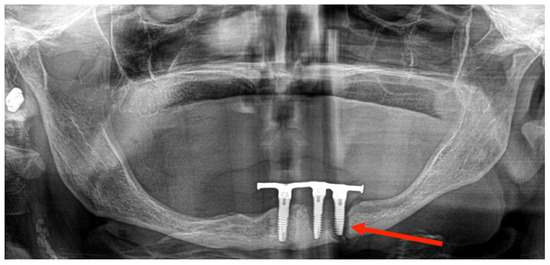

3.1. Case 1